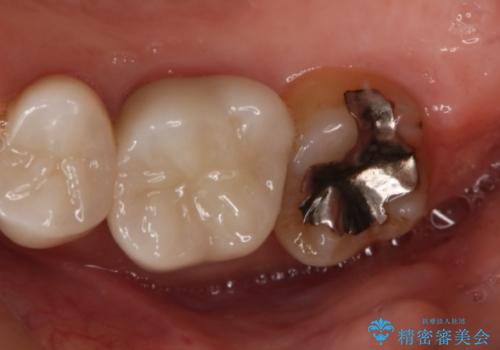

- 右上7番の銀歯のやりかえを主訴に来院された患者様です。

切削量・形態を考慮し、セラミックインレーでの治療を計画しました。